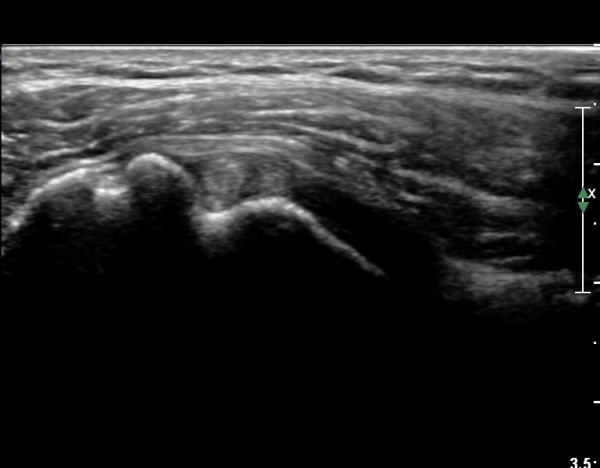

±Ø»ó°Ç Á¾´Ü¸é°Ë»ç¿¡¼­ ´ë°áÀýÀÌ ¿ïÅüºÒÅüÇÏ°Ô º¯ÇüµÇ°í µ¹ÃâµÇ¾î ÀÖÀ¸¸ç ±Ø»ó°ÇÀÇ ÀüÃþ

ÆÄ¿­ÀÌ °üÂûµÈ´Ù. ´ë°áÀýÀÌ »ï°¢±ÙÀ» Ç¥ÃþÀ¸·Î µ¹Ãâ½ÃŰ´Â ¾ç»óÀÌ °üÂûµÇ´Âµ¥ ÀÌ´Â »ó¿Ï°ñÀÌ

»ó¹æÀ¸·Î ÀüÀ§µÈ °ÍÀ» ÀǹÌÇÏ´Â ¼Ò°ßÀ¸·Î ½ÉÇÑ Ãæµ¹ÁõÈıº°ú ȸÀü±Ù°³ ÆÄ¿­ ½Ã °üÂûµÇ´Â

¼Ò°ßÀÌ´Ù(±×¸² 7).